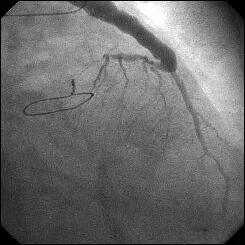

����ALCx take off lesion ��PCI���s���܂����B

CBA(3.5?)+STENT(3.5�~13?)��strategy�ōs������ɂ��Ă��܂������A

��������Stormer(3.5�~15?)��pre������STENT����悤�Ǝv������pre��distal����

�ɑ傫���Ă��܂��A���ǂ����̒ʂ�S670(3.5�~24?)������H�ڂɂȂĂ���

���܂����BCB�������炱��ȂɗȂ����������Ȃ��`�Ƃւ���ł��܂��܂����B

�ꉞ�A���ʂ�Y�t���܂��B

|

|

|

����������������������������������������������������������������������������

�����ł��B

��y�҂Ȃ���A�l�Ȃ�̈ӌ��������Ă��������܂��B

DCA �� Rota ������Ă���{�݂͂Ƃ������A���i�K�ł͖w�ǂ̎{�݂ł�

PCI �͍ŏI�I�ɃX�e���g�𗯒u����Ă���Ǝv���܂��B�����ŁA�X�e���g�O��

pre-dilatation �ł����A�ŏI�I�ɗ��u���悤�ƍl���Ă���X�e���g�T�C�Y���

one-size down �̃o���[���T�C�Y���g�p����Adissection �͈̔͂͒Z���čςނ̂ł�

�Ȃ��ł��傤���H�i�����搶�̉摜�ł́A3.5mm stent �� compatible �ȃT�C�Y��

�悤�Ȃ̂ŁApre-dilatation �� 3.0mm �Ŏ{�s����A����قǂ̒����𗣂�

�����Ȃ������̂ł͂Ȃ����Ǝv����ł��B�jEvidence �����S�ɂ͓����ĂȂ��ɂ��Ă�

�o���ォ����X�e���g�̒����͒Z���ق����ċ����Ȃ��悤�Ɋ����܂����B